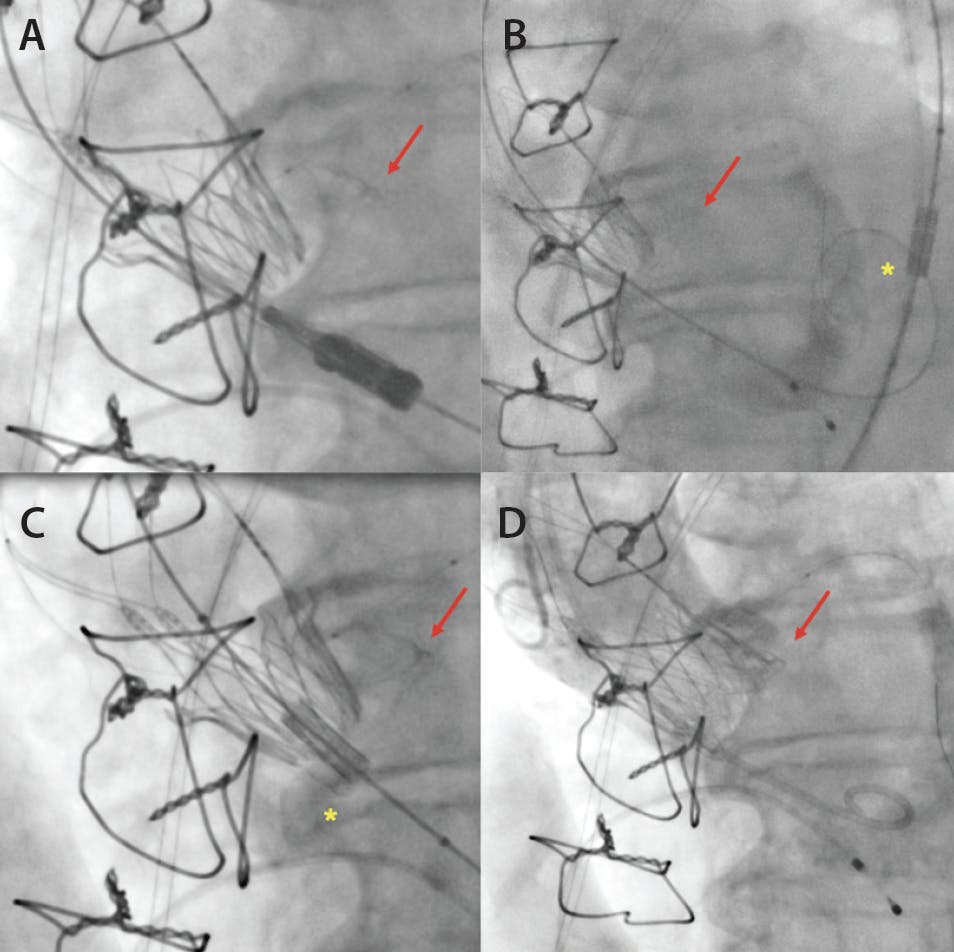

Figure 3. SIVI for a malpositioned valve in a surgical bioprosthesis. Malpositioned Acurate Neo valve in a Trifecta 21-mm bioprosthesis (Abbott) (red arrows; A). Panel B shows the advancement of a stent crimped on a balloon (asterisk), which is implanted in the inflow part of the Acurate Neo valve under rapid ventricular pacing (C). Final aortography shows a good result without aortic regurgitation (D).